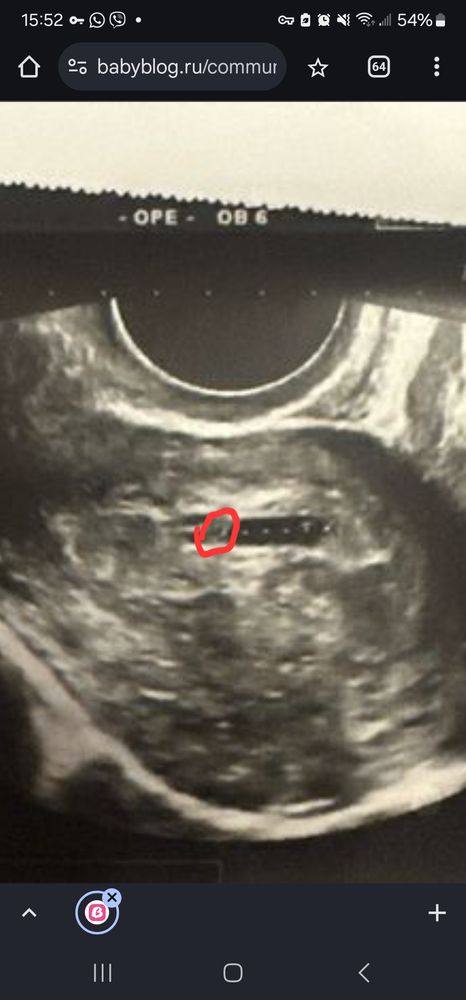

Lilly , а вот это не колечко ? Или мне кажется ? Изображение

23.01.2025

Анна, похоже, да, это фото просто четче)

Lilly , вроде слева в углу ЖМ

Lilly , Изображение